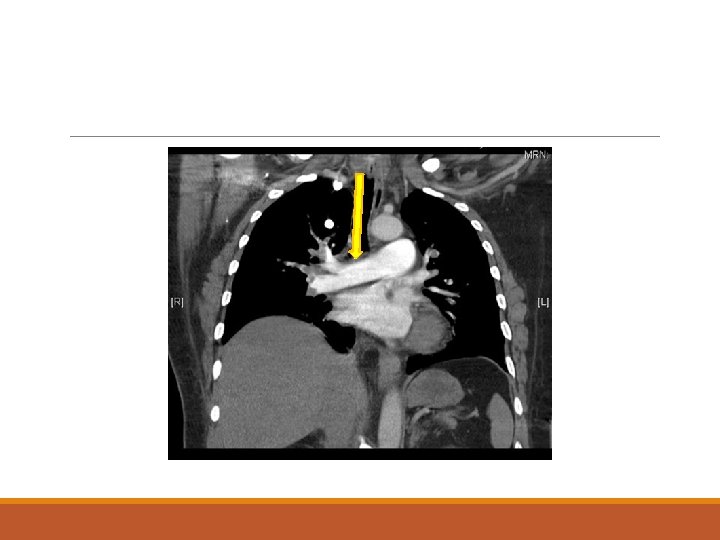

An urgent CT aortogram was ordered. Please comment on the images.

4. What is your final diagnosis? What is the immediate bedside treatment and how would you perform it?